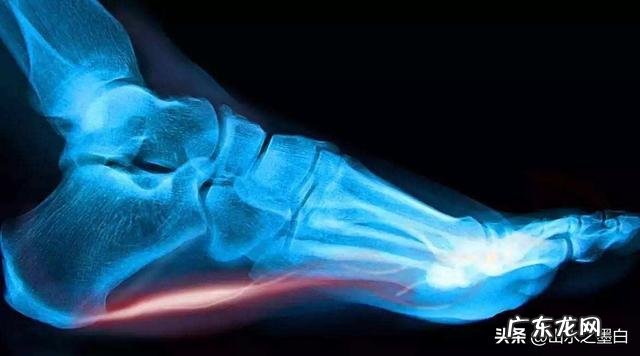

4.足底跖腱膜炎:跖腱膜能维持足弓正常缓冲震荡 。长时间走路或者过度负重,可引起跖腱膜的劳损,最后导致无菌性炎症,进而出现疼痛 。

这个部位的疼痛主要来源于两个部分,一个是止点位于此的跖腱膜,另一个是跟骨前结节部位的滑囊炎、脂肪垫等 。前者跟足底受牵拉时的疼痛更有关系,而后者主要是足跟部局部触地时的疼痛 。临床上恐怕只有医生可以帮你分辨,因为两者离得太近,普通人自己不易区分 。

当然,对于跖腱膜跟骨止点的损伤,还应该将足弓也垫起来,减少其受力 。这样才可能较快的好转 。另外,这个病恢复的很慢,千万不能着急,尤其不要轻易地打封闭,否则就很不容易完全康复了 。